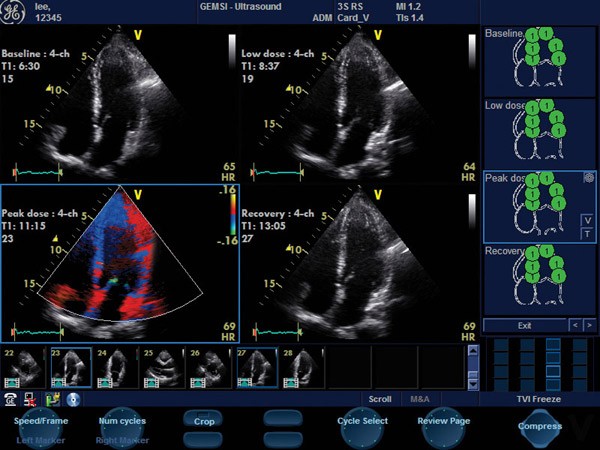

Próba dobutaminowa -  jest powszechnie uznaną, zasadniczo bezpieczną, nieinwazyjną metodą, polegającą na monitorowaniu pracy serca za pomocą echokardiografu przy zwiększającym się obciążeniu lekiem – DOBUTAMINĄ.

Próba dobutaminowa ma na celu kontrolowaną prowokację ewentualnego niedokrwienia mięśnia sercowego oraz ocenę stopnia uszkodzenia mogącego świadczyć o chorobie wieńcowej jej zaawansowaniu oraz o konieczności wykonania koronarografii.

Echokardiografia dobutaminowa u chorych po zawale serca posiada wysoką wartość w ocenie żywotności określonego obszaru mięśnia serca oraz prognozowaniu powrotu funkcji skurczowej lewej komory u pacjentów leczonych pierwotną angioplastyką (PCI) lub metodą przęsłowania naczyń wieńcowych (CABG).